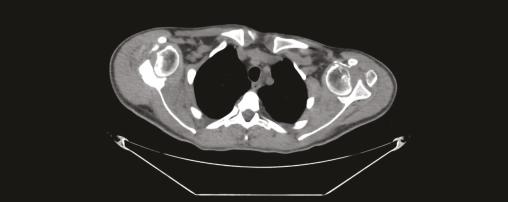

Un homme de 21 ans est admis en service de réanimation pour convulsion fébrile, quelques semaines après avoir été rapatrié d’une mission en zone d’endémie palustre pour des crises convulsives. Le diagnostic d’un accès palustre à Plasmodium falciparum est confirmé. L’évolution est marquée par la survenue d’un déficit moteur et sensitif au niveau des deux membres supérieurs avec une amyotrophie des muscles de la ceinture scapulaire ; un syndrome de Parsonage-Turner post-infectieux est suspecté (fig. 1 ). Un électromyogramme, une imagerie par résonance magnétique (IRM) du plexus brachial (fig. 2 ) et un scanner des épaules sont en faveur d’une luxation antérieure post-convulsive des deux épaules (fig. 3 et 4 ).

Les radiographies standard contribuent à poser le diagnostic ; le scanner permet d’appréhender le siège exact et l’étendue des lésions osseuses de passage antérieur.